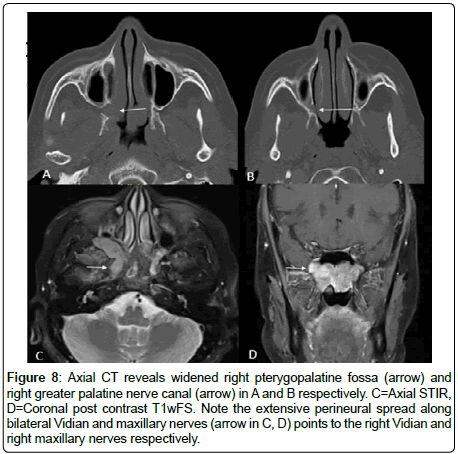

3 cases of adenoid cystic carcinoma revealed perineural spread (Figure 8).

Figure 8: Axial CT reveals widened right pterygopalatine fossa (arrow) and right greater palatine nerve canal (arrow) in A and B respectively. C=Axial STIR, D=Coronal post contrast T1wFS. Note the extensive perineural spread along bilateral Vidian and maxillary nerves (arrow in C, D) points to the right Vidian and right maxillary nerves respectively.